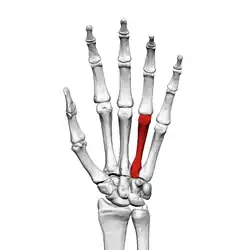

Fourth metacarpal bone

![]() Fourth metacarpal of the left hand (shown in red). Palmar view. | |

The fourth metacarpal bone (metacarpal bone of the ring finger) is shorter and smaller than the third.

The base is small and quadrilateral; its superior surface presents two facets, a large one medially for articulation with the hamate, and a small one laterally for the capitate.

On the radial side are two oval facets, for articulation with the third metacarpal; and on the ulnar side a single concave facet, for the fifth metacarpal.